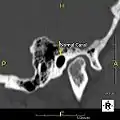

Normal ear canal

The normal ear canal is approximately 7 mm in diameter and has a volume of approximately 0.8 ml (approximately one-sixth of a teaspoon).[4] As the condition progresses, the diameter narrows and can even close completely if untreated, although sufferers generally seek help once the passage has constricted to 0.5-2 mm due to the noticeable hearing impairment. While not necessarily harmful in and of itself, constriction of the ear canal from these growths can trap debris, leading to painful and difficult to treat infections.